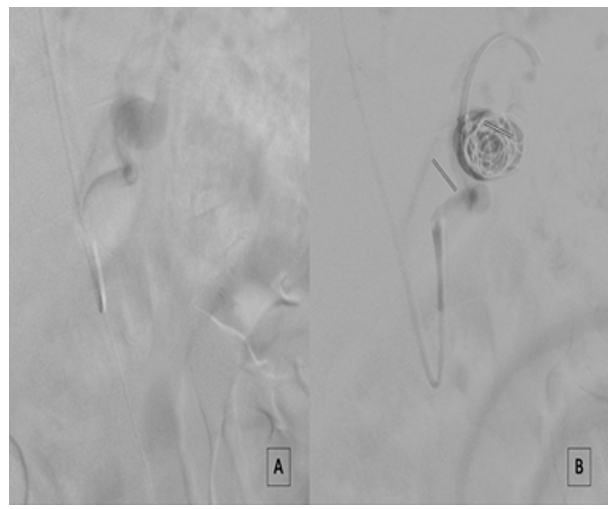

An introducer sheath was inserted via the vascular access and ad- ministered 2500 IU of heparin. The origin of the CT and subse- quently the splenic artery were engaged using a 5F C2 or Simmons catheter. Subsequently a 5F Flexor sheath (Cook Medical, Bloom- ington, IN, US) introducer was advanced until the CT origin; a 45 cm length or a 90 cm introducer length was employed for the femoral or the brachial access respectively. Multiplanar pre-proce- dural arteriograms were performed to determine the SAA charac- teristics and confirm CTA findings. The SAA was cannulated using a .018 wire (Command; Abbott Vascular, Santa Clara, CA, US) or a .014 wire (Balance Middle Weight -BMW, Abbott Vascular), and a Rebar 18 microcatheter (EV3, Irvine, CA, US) was positioned into the SAA. At this stage, the Concerto Helix Detachable Coil System PGLA-fibered (Medtronic, Inc., Minneapolis, MN, US) was deployed inside the SAA until the aneurysm sac completely felling (Fig 2).

Figure 2: Intraoperative Imaging Showing (A-B) Splenic Artery Aneurysm Detachable Coil Embolizazion Filling And (C) Final Ar- teriography After Coils Deployment.

Coils number and dimension depended on the size of the aneurysm; as general principle larger and longer coils were employed at the filling beginning; smaller coils were employed to achieve a moderate SAA packing. A reduced contrast media caption into the SAA was evident in association to a 15-20% moderate volume coil packing (Fig. 3).

Figure 3: Intraoperative Imaging Showing (A) Splenic Artery Aneurysm Arteriography Before Coil Embolization Filling And (B) After Moderate (18%) Coil Packing Embolization With A Reduced Contrast Media Caption.